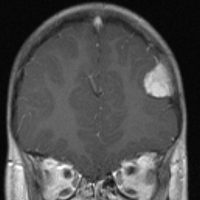

3歳の子どもの髄芽腫の放射線治療後に生じた脳萎縮

3歳の髄芽腫です。発症時から小脳表面や小脳橋角部を含めて転移がありました stage M2。化学療法で腫瘍はかなり縮小して,3歳7ヶ月まで頑張ってから,後頭窩照射 25.2グレイ14分割と脳脊髄照射 CSI 28.8グレイ16分割の放射線治療をしました。当時このような例では,脳脊髄照射 36グレイが標準治療でしたから,これでもかなり線量を落としました。

左側の画像は照射後4ヶ月目です。延髄の左側に放射線壊死が生じました。これは数ヶ月かかってゆっくり消褪しました。右側の画像は照射後1年くらいのものです。大脳白質にびまん性に萎縮性変化がみられます。典型的な放射線治療による白質萎縮です。この程度の線量でも脳壊死や全脳萎縮を生じない子どももいます。

放射線の副作用は同じ線量でも個人差がとても大きいです idiosyncrasy